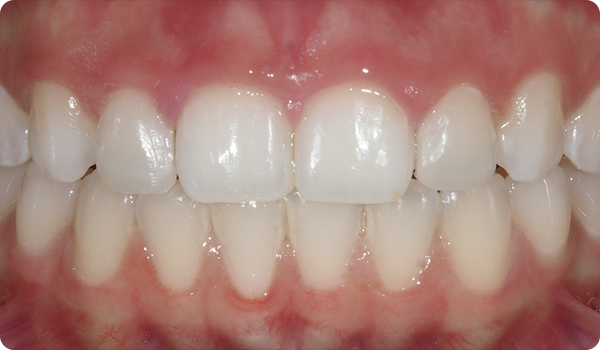

Met Right krijgen je patiënten de glimlach die ze willen in de tijd die ze willen, op een comfortabele en onopvallende manier.

Het uitlijnen van de tanden met Right is de perfecte en meest conservatieve basis voor toekomstige whitening of fineerbehandelingen die de glimlach van de patiënt perfect maken.